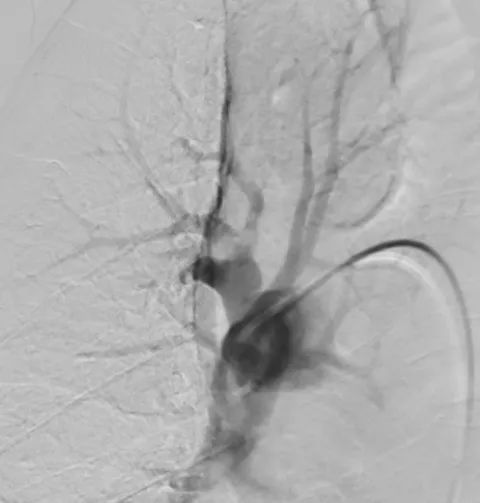

A 66-year-old woman experienced progressive lower limb swelling for 10 days, followed by sudden chest pain, chest tightness, and shortness of breath for 2 days. She was diagnosed with pulmonary embolism at another hospital but showed poor response to medication, with blood oxygen saturation around 80%. After being admitted to our department, emergency interventional thrombectomy and pulmonary artery thrombolysis were performed, raising her blood oxygen saturation to 98% and significantly relieving her chest pain symptoms.

Pre-Surgery

After Thrombus Suction